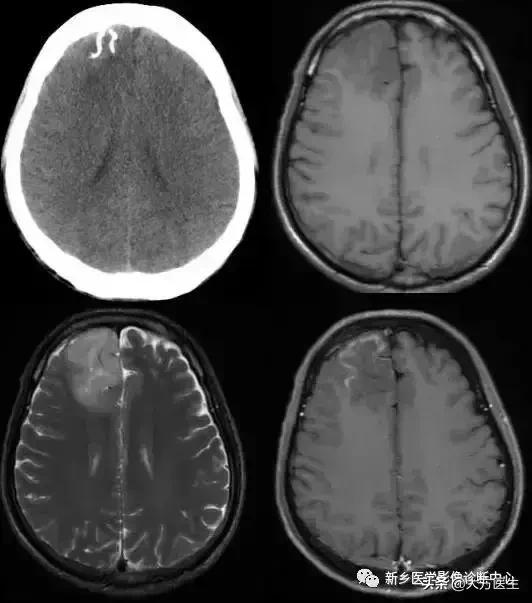

1、少突胶质细胞瘤

多见于青少年,类圆形肿块,边界清楚,密度不均,点片状、弯曲条带状、不规则或皮层脑回状钙化,可能轻度水肿,轻度强化。

MR:为长T1长T2信号,钙化均为低信号。